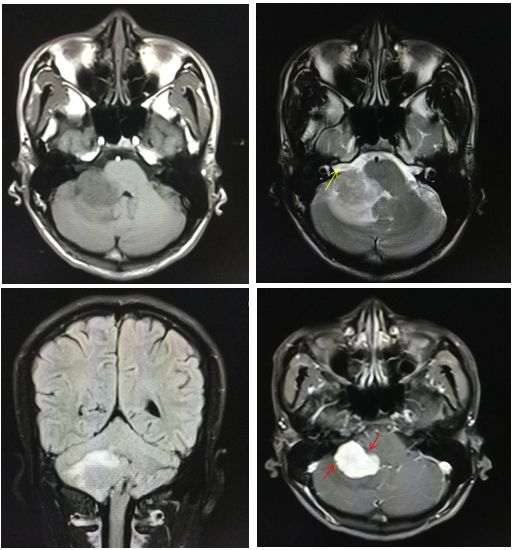

病例7

19岁,男性,头晕头痛来诊。

答案:CPA区弥漫大B细胞淋巴瘤

桥小脑角区(CPA)淋巴瘤非常罕见,文献鲜有报道。本例淋巴瘤发病年龄低,位置特殊,且没有给出DWI序列,无疑增加了诊断难度。不过仔细观察图片不难发现右侧内听道段神经结构完整,故可排除CPA区最常见的神经鞘瘤;病灶整体呈实性,T2WI信号偏低,与脑膜瘤非常相似,但平扫时病灶内侧缘与邻近脑实质分界模糊,增强后边缘有锯齿感及分叶征(红箭),这在脑膜瘤中是非常罕见的,同时病灶本身也缺乏与邻近小脑膜广基底相连的证据。病灶强化相当均匀且大部分边缘非常光滑,可排除掉PCA区相对少见的室管膜瘤、脉络丛乳头状瘤及血管母。